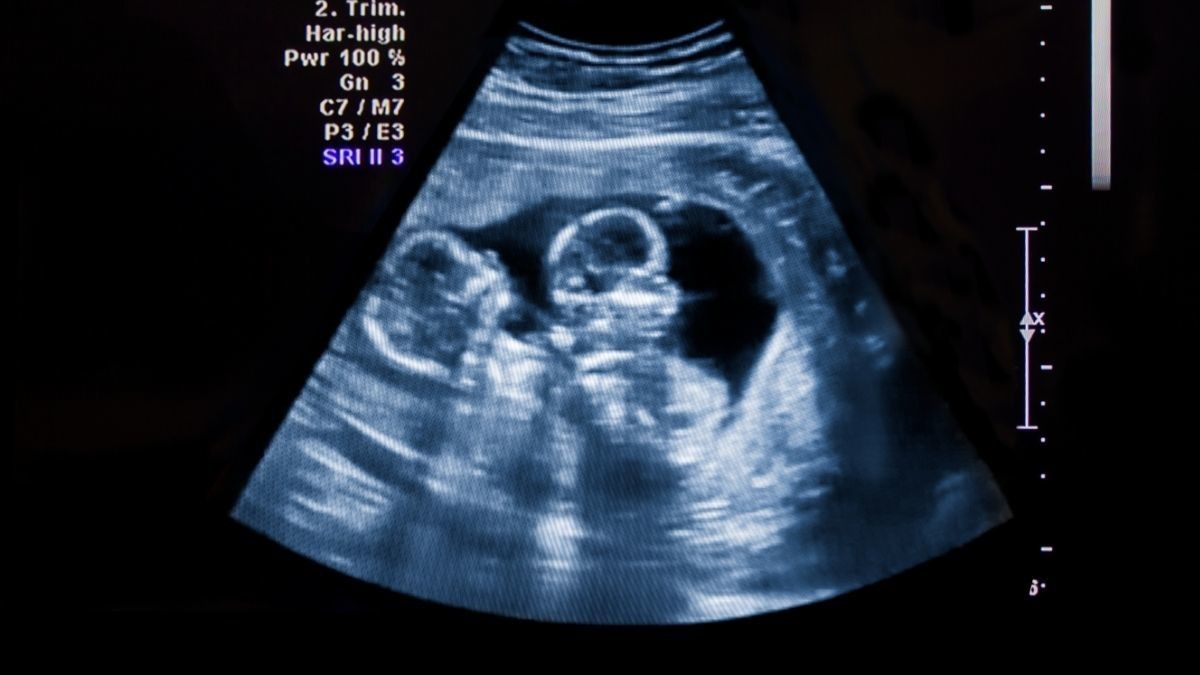

Apa kamu pernah mendengar kehamilan superfetasi? Kejadian langka ini pernah terjadi pada seorang ibu di Arkansas, Amerika Serikat. Ia tidak menyadari sedang mengandung dua janin yang berbeda usia sampai dokter memberitahunya melalui hasil USG.

Superfetasi dicurigai hanya bila si kembar memiliki ukuran dan tahap perkembangan yang berbeda. Hal ini biasanya terlihat selama pemeriksaan USG rutin.